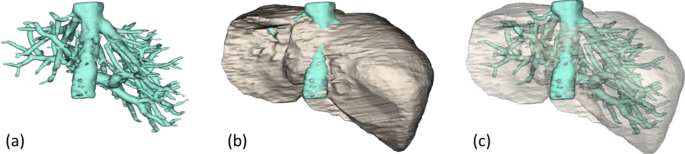

Alternatively, the liver and entire hepatic vasculature could be independently segmented. To this end, parts of the proposed method could be exploited. Particularly, MND and RL, without GC or related constraints, were simultaneously applied to extract interior vessels, which were subtracted from and later fused with the liver. The extracted result is illustrated in Fig. 14. This vessel segmentation process took about additional 1.2 min.

Simultaneous extraction of a liver (b) and its vasculature, including IVC (a), with their fusion (c).